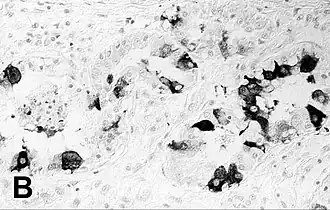

Marquage immunohistochimique du poumon d'un phoque infecté par Phocine morbillivrus.